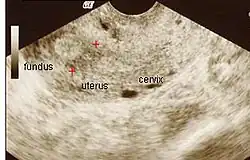

Ultrasound view.

Amniotic sheet on ultrasound